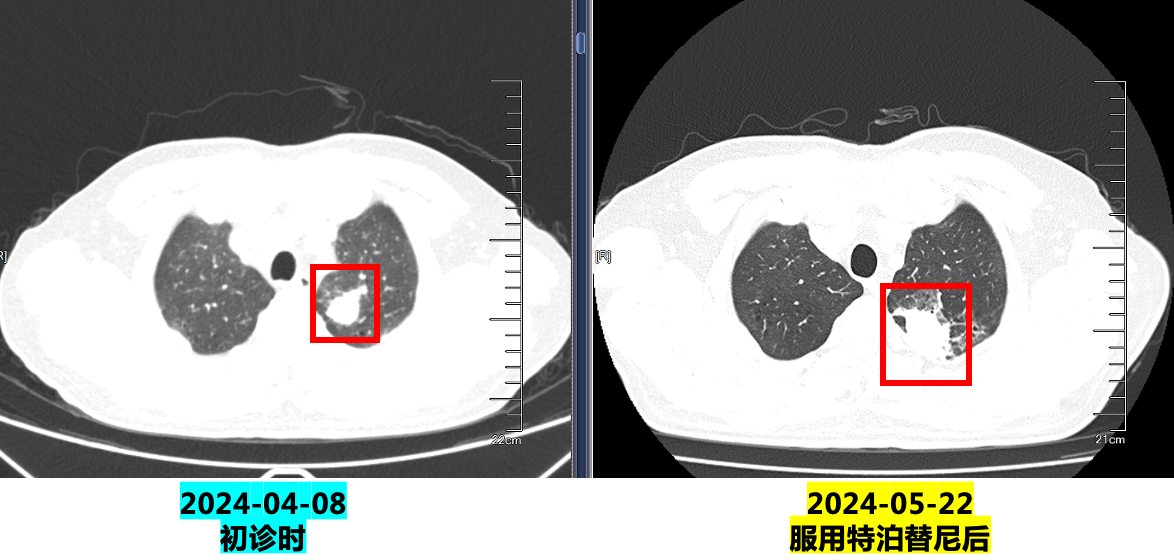

1. 2024.4.22:口服特泊替尼450mg(2片)每日一次。

2.2024.5.22复查:咯血增多,胸部CT示病灶明显增大,评估疾病PD,停用特泊替尼。

3. 2024.5.27:予培美曲塞+卡铂化疗,出现皮疹(口服氯雷他定片后4-5天消退)。

4. 2024.6.17至今:行培美曲塞二钠0.8g + 卡铂400mg + 舒格利单抗1200mg(共20程,维持治疗中,无不良反应)。

疗效评估:PR(部分缓解)。